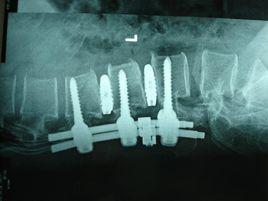

“AD射頻熱凝靶點消融術”是在C型臂X光機精確定位下,用一根直徑只有0.7mm的穿刺針,通過導航系統的精確引導,直接作用在病變的髓核上,進行熱凝消融,使其變性,凝固,收縮減少體積,解除壓迫並修復髓核和纖維環。治療時病人痛苦極小,操作安全,神經監測功能和時間、溫度可控性極高,不會造成對神經根的熱損傷,阻抗的顯示能精確測定出被治療組織的性質。

4、在C型臂透視下,將導引穿刺針到達靶點,逐步下入工作導管,建立工作通道;

“後路法”摘取的椎間盤髓核組織5、放置椎間孔鏡,在鏡下觀察組織結構,避開神經、血管,辨析韌帶與纖維環與髓核;

8、用雙極電凝或離子體清理工作創面,耐三氧的椎間孔鏡,可經鏡上特製的入口注入33-38ug/ml 的三氧效果更好,拔出工作導管,縫合切口,無菌紗布包紮創口。